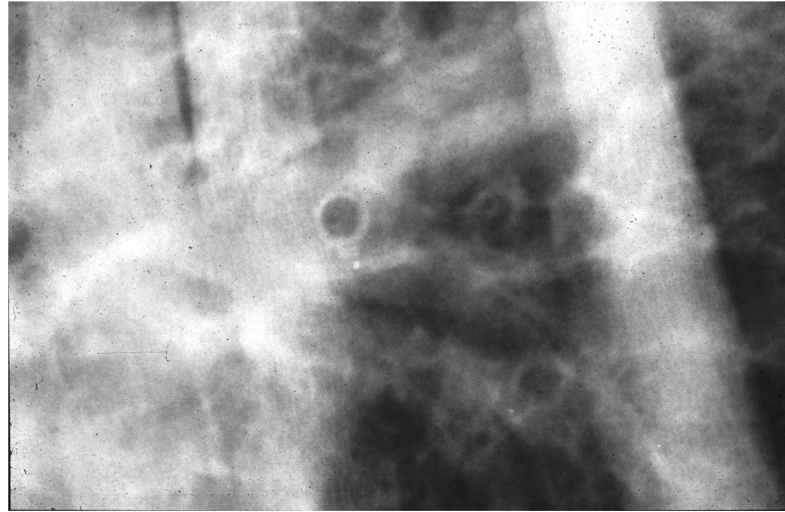

We can see tramlines and donuts. Which lung pattern is shown here?

Interstitial

This is like looking through mist or a lace curtain; structures are not obliterated, but are greyed-out.

Donuts and tramlines = abnormal thickening of the airway (bronchiole) walls -> bronchial pattern